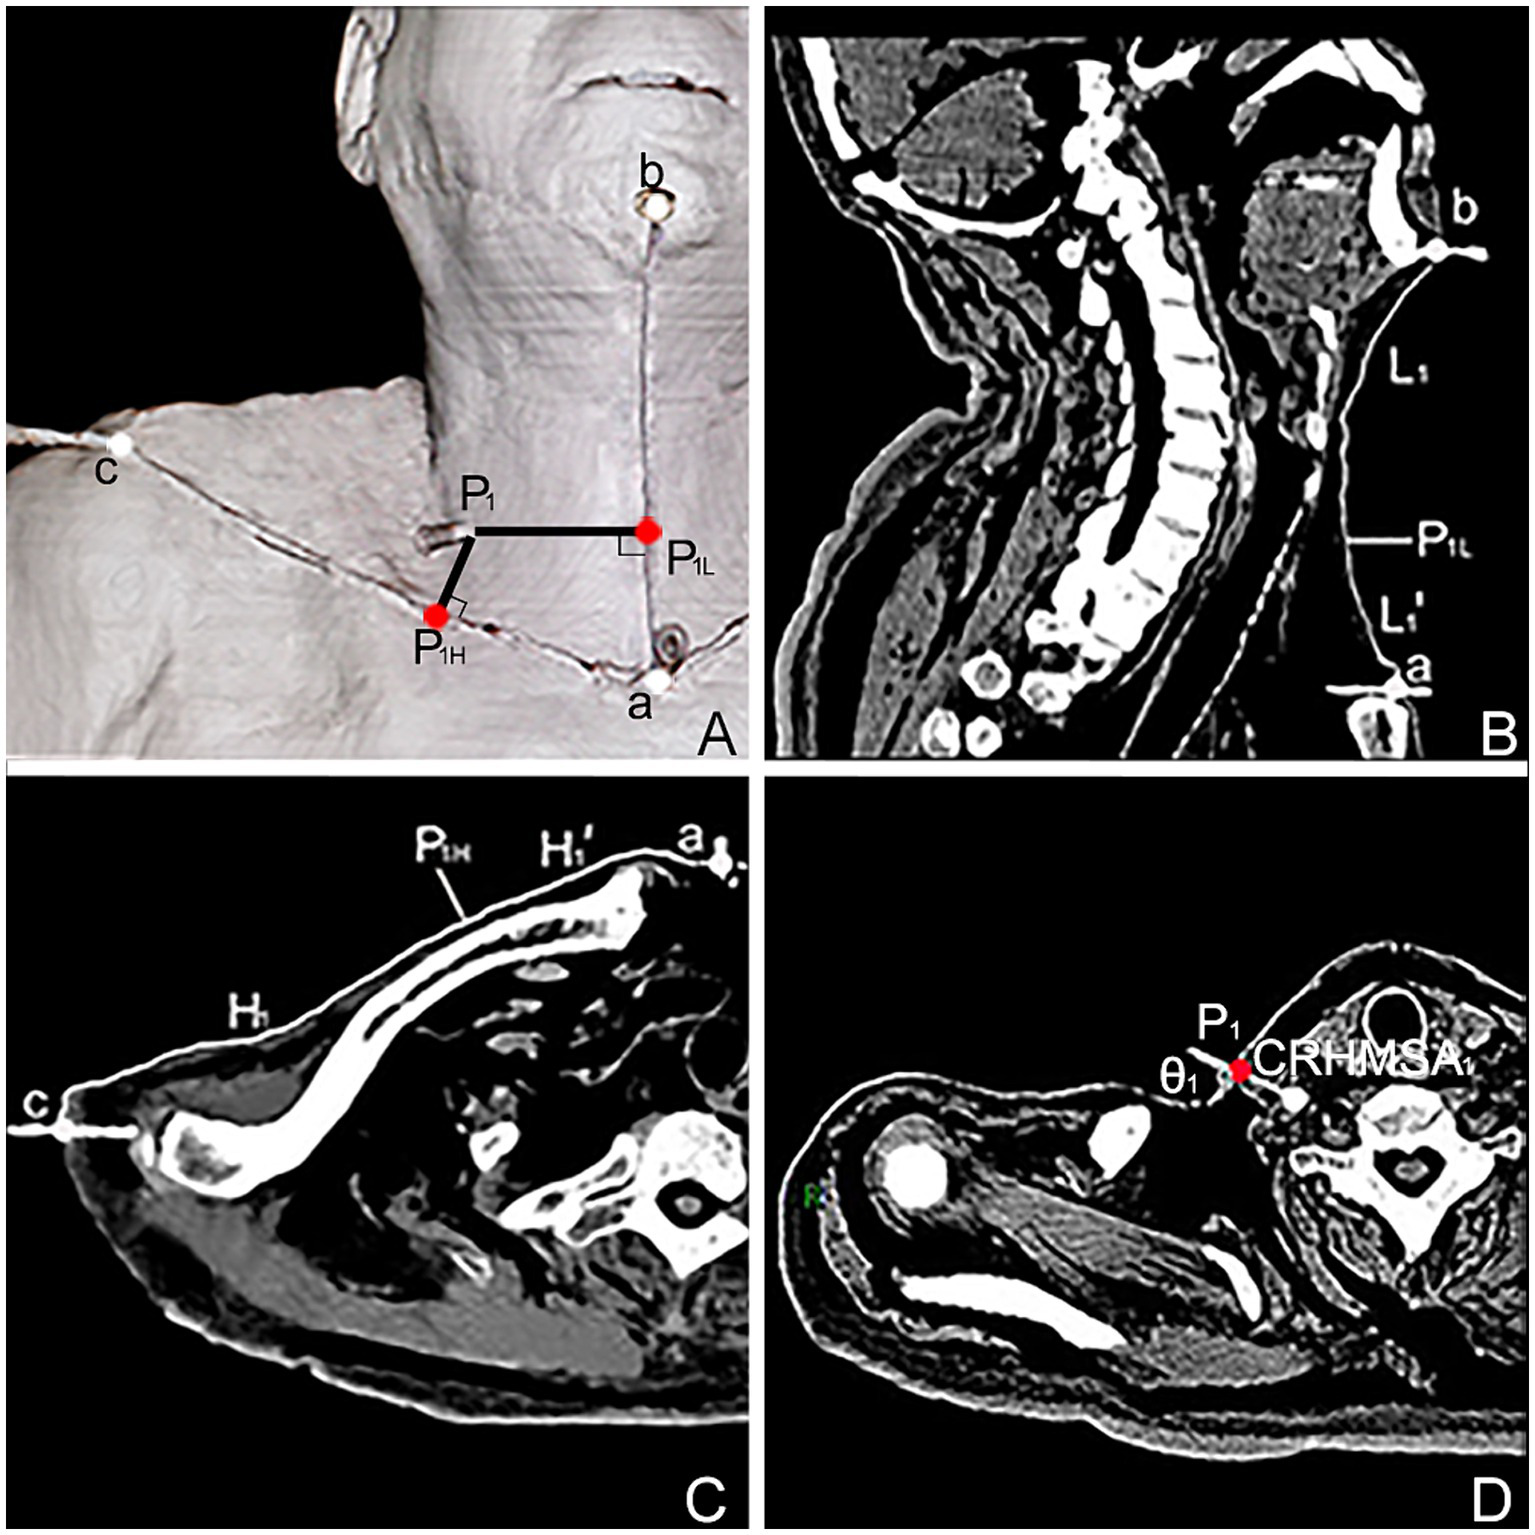

Figure 4

Spiral CT localization image of the center of the highest region of muscle spindle abundance (CRHMSA1) of the right SA muscle in males. (A) Three-dimensional reconstructed spiral CT image showing the position of CRHMSA1 on the body surface and the designed reference line. P1 is the surface projection point of the SA muscle CRHMSA1. P1H = intersection point generated by creating a line perpendicular to line H through P1. P1L = intersection point of the H-line passing through P1 and the L-line. a-P1H=H1’, a-P1L = L1’. (B) Lengths of the L and L1 lines in the coronal plane were measured. (C) Measure the lengths of the H and H1’ lines on the section passing through line H. (D) Determine the depth and angle of needle insertion for CRHMSA1 in the cross section.

The surface projection point (point P) of the CRHMSA projected the percentage position on the reference line, along with the angle between the puncture needle and the skin at the P point and the depth of the CRHMSA, as shown in Table 2. No statistically significant differences were observed between the left and right sides or between males and females (p > 0.05) (Tables 3–5). This article includes a spiral CT localization image of the CRHMSA, using the right SA muscle as an example (Figure 4).

The projection points (P) of the CRHMSAs on the anterior surfaces of the neck is denoted as point P, the intersection of a straight line passing through point P, which is perpendicular to the H line, with the H line is denoted as PH (P1H-P5H). Similarly, the intersection of a horizontal line passing through point P and the L line is denoted as PL (P1L-P5L). The distance from point a to point b is equal to the length of the L line. The distance from point a to point c is equal to the length of the H line. The distance between points a and PH is denoted as H′ (H1–H5’), and the distance between points a and PL is denoted as L’ (L1–L5’). Calculations were performed for H′/H × 100% and L’/L × 100% to determine the percentage position of point P on the body surface. Additionally, the sharp angle between the puncture needle and the skin was recorded as θ1, θ2, θ3, θ4, and θ5. Measurements were taken for the angle θ and the depth of the CRHMSA.